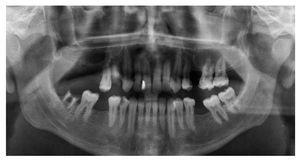

En la visita a nuestra clínica el paciente refirió un dolor en la zona del seno maxilar izquierdo. En la radiografía panorámica practicada se observó un seno maxilar izquierdo completamente velado y un engrosamiento de la mucosa basal en el seno maxilar derecho (fig. 1). Se identificaron además diversos dientes que requerían tratamiento odontológico. Debido al gran malestar del paciente, se realizó una tomografía volumétrica digital dental (TVD) para el estudio diagnóstico de los demás senos paranasales.

Figura 1. Radiografía panorámica.